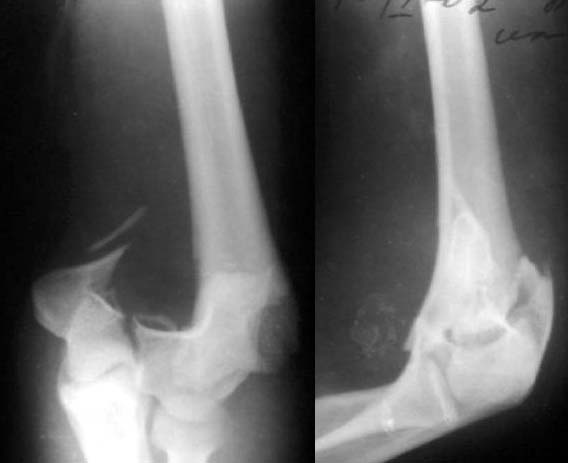

До лечения

Лечение тут, видимо, должно основываться в первую очередь на открытой репозиции, поскольку возможности закрытой при таких повреждениях далеко недостаточны. Если поверхность блока состоит не просто из двух крупных фрагментов, лучше идти с отсечением локтевого отростка. Вопрос о методе фиксации более второстепенный. Можно и аппаратом. В приложении - пример лечения такого повреждения с внутренней фиксацией.